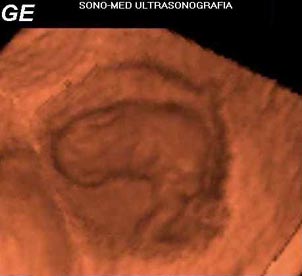

La figura 2

corresponde a un embrión de 8 semanas, de 13.7 mm de longitud cráneo-caudal,

ubicado dentro de su saco gestacional. Se aprecia el saco vitelino cercano

al polo cefálico y una extremidad superior. El barrido se realizó

con US transvaginal. Creemos que al aplicar una técnica para ver

la superficie fetal se pueden identificar mejor algunas estructuras, como

lo son las extremidades y manos a esta edad gestacional.